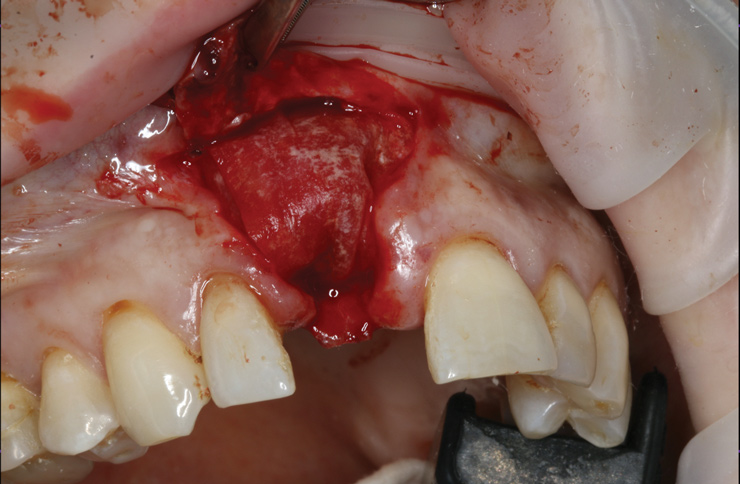

8. Tooth No. 8 with diagnosis of Grade III socket, requiring extraction followed by guided bone regeneration and a rotated pedicle flap to gain hard and soft tissue for future implant placement.

Figure 8

9. Tooth No. 8 with diagnosis of Grade III socket, requiring extraction followed by guided bone regeneration and a rotated pedicle flap to gain hard and soft tissue for future implant placement.

Figure 9

10. Tooth No. 8 with diagnosis of Grade III socket, requiring extraction followed by guided bone regeneration and a rotated pedicle flap to gain hard and soft tissue for future implant placement.

Figure 10

11. Tooth No. 8 with diagnosis of Grade III socket, requiring extraction followed by guided bone regeneration and a rotated pedicle flap to gain hard and soft tissue for future implant placement.

Figure 11

Based on the single extraction socket roadmap developed by El Chaar and colleagues, the socket of tooth No. 8 was diagnosed as Grade III and would require initial treatment that included the extraction of failing tooth No. 8 followed by simultaneous guided bone regeneration and soft-tissue augmentation by means of a rotated palatal pedicle flap (Figure 8 through Figure 11).27,28 The principles of and guidelines for both the ridge augmentation and rotated pedicle flap have been described in the literature and will not be focused on in this case report.27-30 The patient was temporized with a bonded Maryland bridge that was adjusted to avoid creating pressure on the tissue during healing (Figure 12).